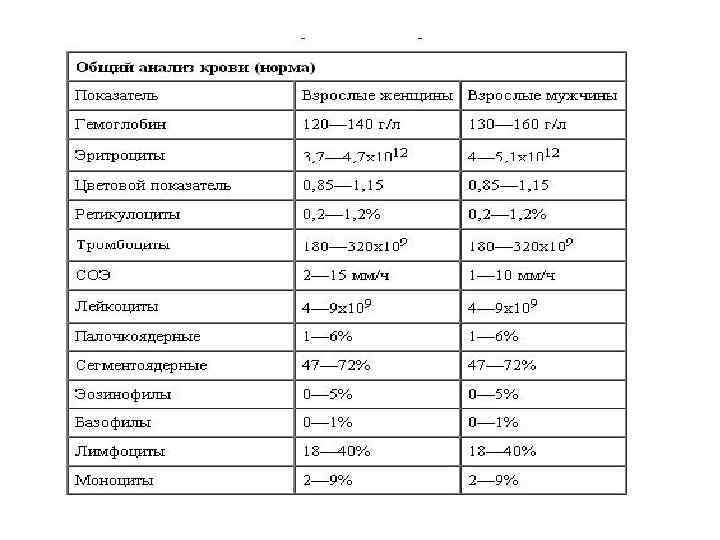

Лабораторные методы исследования • Анализ крови клинический: лейкоцитоз, сдвиг лейкоцитарной формулы влево, ускорение СОЭ, при тяжелых пневмониях – лейкопения. • Анализ крови биохимический: повышение содержания фибриногена, серомукоида, сиаловых кислот, глобулинов, появление С-реактивного белка. • Анализ мокроты клинический: • Анализ мокроты бактериологический с посевом на флору и чувствительность к антибиотикам. • Анализ мочи общий: умеренная протеинурия, единичные эритроциты